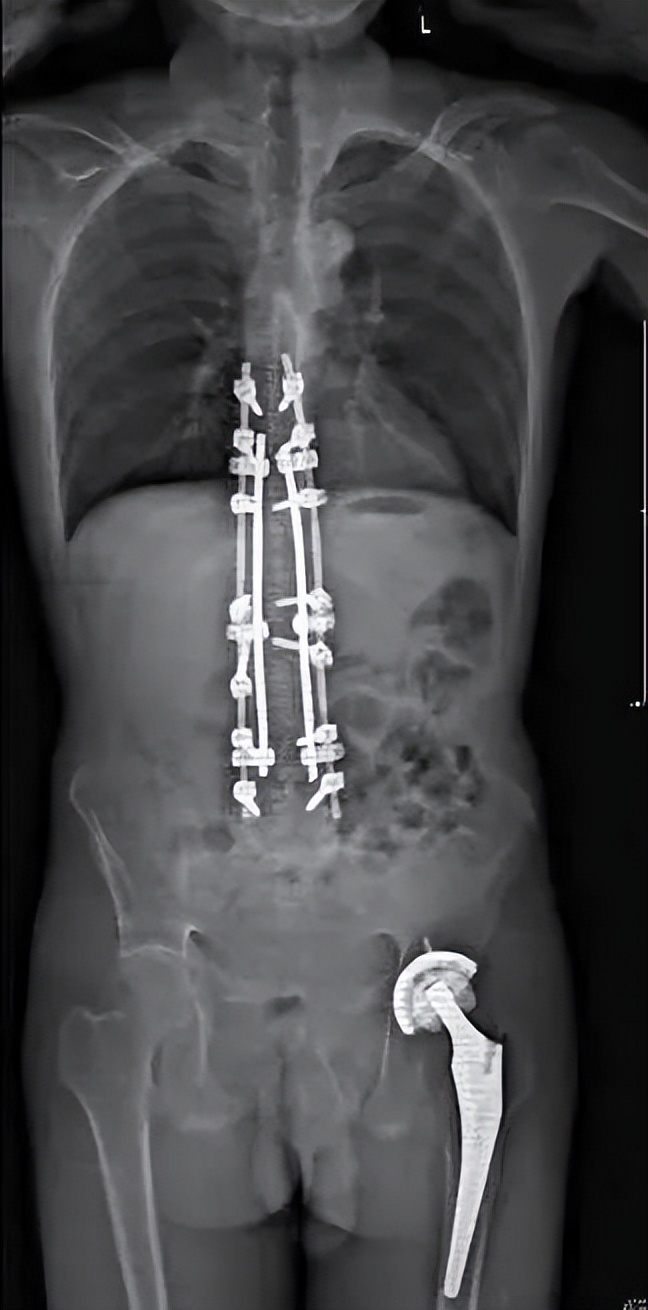

患者又回到了最信任的北京积水潭医院,找到了髋关节手术的主刀医生周一新主任,由周主任介绍到脊柱外科。脊柱外科经过全科查房讨论,制定周密的术前规划,综合考虑患者的直立、平视、端坐、平躺等功能,设计截骨位置并计算截骨角度,最终确定了L3、T12双节段经椎弓根截骨的矫形方案。在麻醉科、手术室、肌电图室、ICU、输血科、脊柱外科等多方面合作下,手术顺利完成。患者术后即可完全平躺,下地后可完全直立并且平视。手术效果非常满意,患者重新挺起胸膛,开启新的人生。